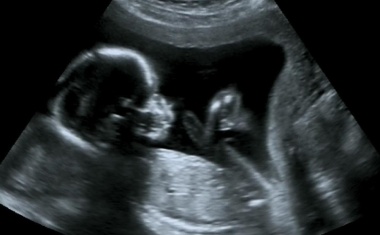

Jedes Jahr kommen in Deutschland Tausende Babys viele Wochen zu früh auf die Welt und müssen sich oft monatelang ins Leben kämpfen. Je früher die Babys geboren sind, desto höher ist das Risiko für lebensgefährliche Komplikationen. Infektionen können zu einer Sepsis führen und gehören zu den häufigsten Todesursachen.